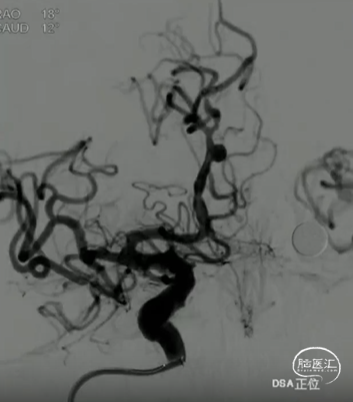

术前影像

· 患者三型弓,奇大脑前A3段动脉瘤,形态极不规则,血管入路极其迂曲

· 从大脑前动脉瘤起始段,有广泛伴有动脉粥样硬化的斑块

· 病变远端处于奇大脑前动脉双分叉位置,远端支架可着陆的空间较短,远端血管较细,且伴随斑块